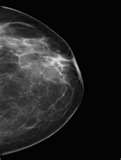

Last week I was called back to the breast center because my mammogram from the week before was abnormal... This frightened me... Mostly because cancer runs rampant in my family... My dad suffered from oral cancer and passed a couple of years ago and My mom had a double mastectomy this month...

I was advised that I would have another mammogram on my left breast and they would do an ultrasound... I was told that I would be informed of their findings in that visit... They were able to get a more clear mammogram (they squeezed the crap out of my boob).. and the ultrasound showed a pretty good sized cysts.. The cyst was filled with fluid and was no cause for concern... The doctor advised me that I am at an extremely high risk for breast cancer because... My breast tissue is not mostly fat like most - the tissue is very nodular and tough.. Very hard to read... Both maternal and paternal grandmothers had breast cancer.. My mother had breast cancer... Numerous relatives have had ovarian cancer and breast cancer... He advised me to meet with a geneticist, a breast surgeon, AND my gynecologist oncologist (I had first stages of vaginal cancer years ago) to discuss my options... He said that studies have shown that removal of the ovaries or breasts can reduce the likelihood of cancer by about 90%..... The doctor also advised that I will need to be checked every 6 months with a mammogram, ultrasound, and MRI...